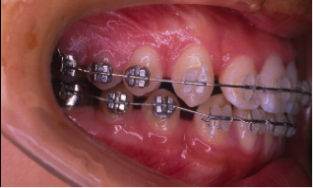

叢生(そうせい)

20歳/女性

悩み:歯がデコボコ

八重歯が押し出されて歯がでこぼこに並んでいる状態

治療期間:約2年4ヶ月

治療前

治療後

奥の歯が倒れて狭くなっている台形の歯列を広げて歯を起こす治療で、奥の歯が見えるようになるUの字型に治しました。

上の歯下の歯、それぞれ2本づつ第一小臼歯を抜歯した治療となりました。

歯を見せて笑えるようになり喜んでもらいました。